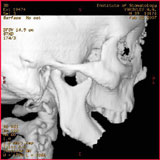

СК томограмма пациента с дефектом нижней челюсти после огнестрельного ранения (а), моделирование замещения дефекта аутотрансплантатом из малоберцовой кости по данным СКТ (б)

КТ головы проводят в горизонтальном положении. Специальной подготовки не требуется. Обычно достаточно 15 виртуальных срезов головы. Об уровне среза можно легко судить по форме, положению и размерам желудочков мозга, а так же патология кости черепа, например остеомы. После выполнения срезов возможна реконструкция объемного изображения или увеличенного изображения отдельного участка мозга или кости.